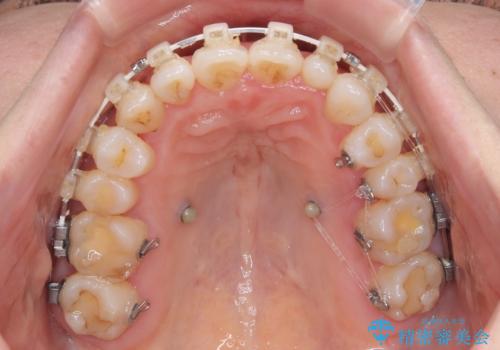

骨格的なズレを歯列矯正でカバー ワイヤー装置での非抜歯矯正

- 前歯のデコボコと咬み合わせの悪さを気にして来院された患者様です。

下顎骨が左側にズレて成長してしまったため、左側の咬み合わせが上下反対になっている状態でした。

骨格的なズレは歯列矯正のみでは改善できず、骨切除が必要となります。

そこまでの処置は望んでいらっしゃらなかったため、歯列矯正でのカムフラージュにより咬み合わせを改善することとしました。

予想通り左側の咬み合わせの調整に苦労をしましたが、最終的には違和感のない咬み合わせを達成することができました。